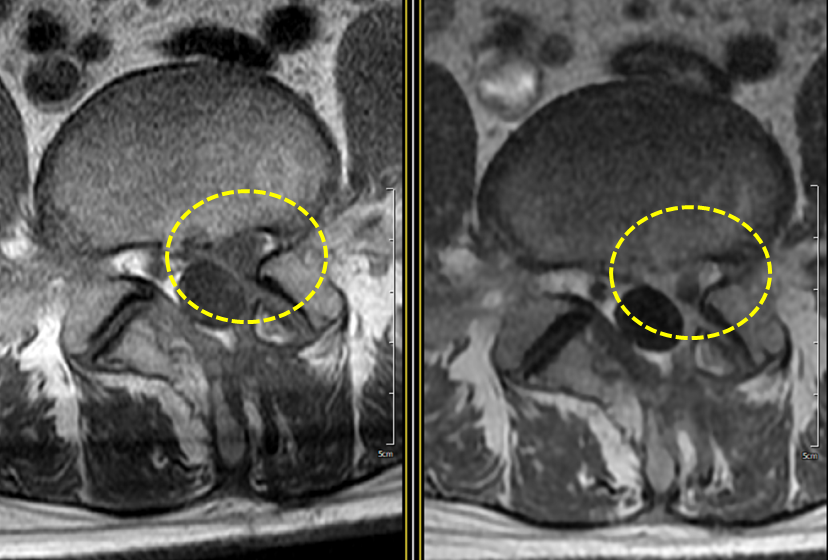

These contractions may be closely related to spinal disc issues. When a disc presses on a nerve, the connected muscles can react abnormally, leading to spasms, tremors, or involuntary contractions. Lumbar disc problems, in particular, can trigger these reactions along the nerve pathways that run into the legs or buttocks. This can interfere with daily activities and sometimes result in severe pain. If such symptoms are mistaken for simple muscle strain and dismissed, treatment might be delayed—so accurate diagnosis is important.